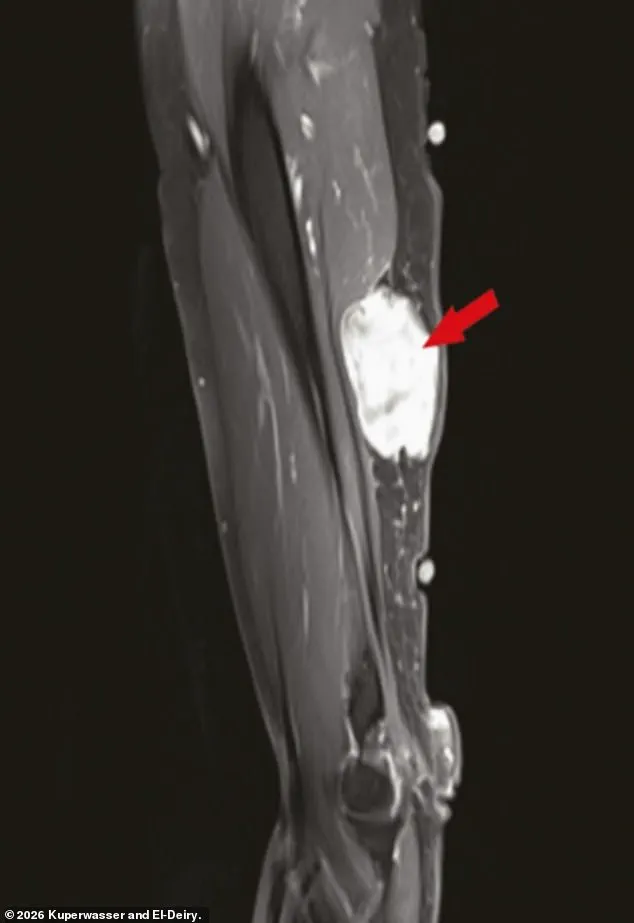

El-Deiry and Kuperwasser's analysis also uncovered several intriguing case reports.

These included instances of tumors developing near injection sites in the arm, a phenomenon that the authors suggested warranted further investigation.